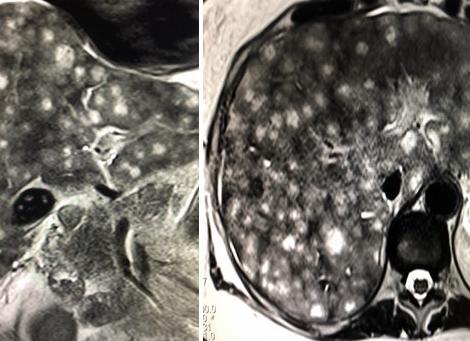

Наиболее современный метод диагностического обследования, который, в свою очередь, позволяет получить наиболее достоверную информацию не только о строении, но и о полной работе органа – МРТ. При помощи этого метода диагностического обследования, можно выявить нарушения не только в печени, но и в иных органах, например: мочевом пузыре, жёлчном пузыре, 12-перстной кишке и т.д.